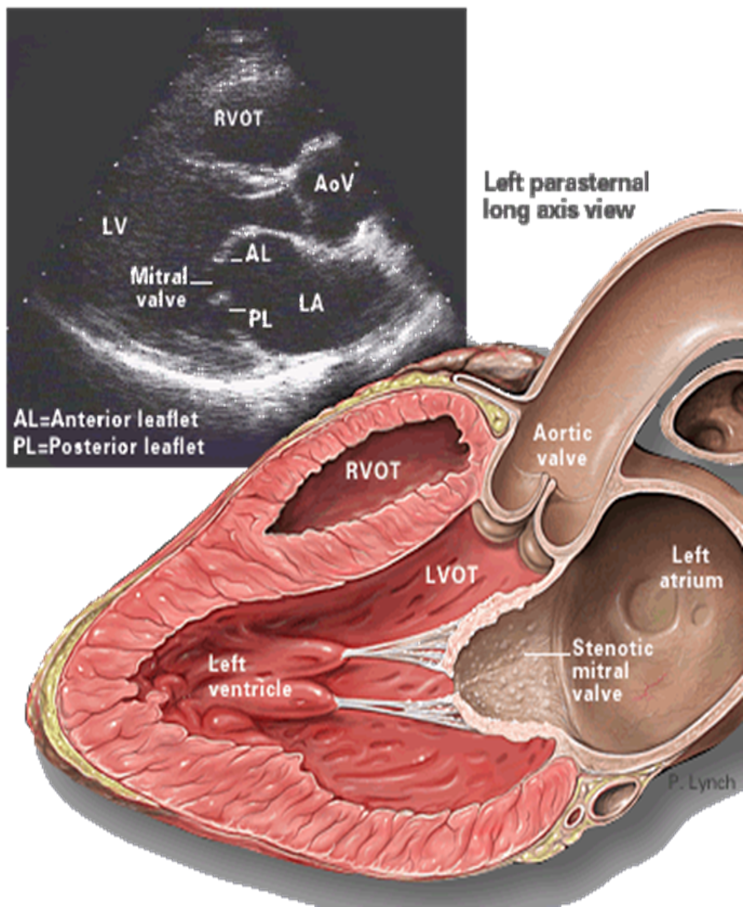

• TTE (Transthoracic echocardiography): best initial test to evaluate the mitral valve and quantify the anatomical extent of the stenosis.

Findings

• Reduced mitral valve area (MVA): ≤ 1.5 cm² (severe)

• Thickened, calcified leaflets with commissural fusion

• Increased mean diastolic pressure gradient across the mitral valve

• RV dilation

• LA enlargement

• Evidence of pulmonary hypertension